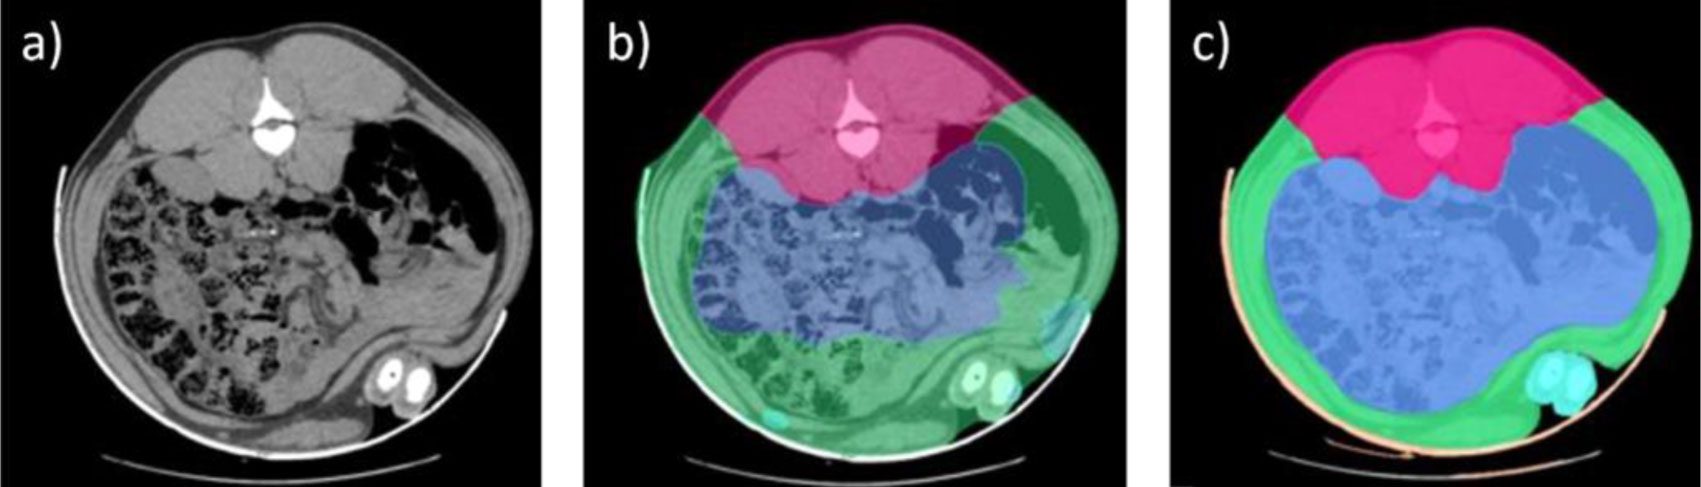

O processo de análise de imagens foi realizado manualmente durante anos, identificando as diferentes áreas anatómicas e os tipos de tecido (osso, gordura e músculo), o que já representava um avanço significativo. Em 2016, foi implementado um método mais automatizado de análise de imagens por TC, permitindo a diferenciação dos diferentes cortes principais (presunto, pá, lombo e barriga). O aparecimento das tecnologias de Inteligência Artificial (IA) foi fundamental para a automatização deste processo, essencial para o escalonamento desta ferramenta e o aumento da eficiência do número de animais analisados.

No obstante, la IA requiere de un proceso de entrenamiento previo para lo cual es necesaria una base de datos enorme con imágenes previamente analizadas que sirvan de modelo. En nuestro caso, esa base de datos estaba disponible gracias a los años previos de análisis con TC, durante los cuales ya se había avanzado notablemente en la segmentación de los tejidos e identificación en la imagen de los voxel (unidades más pequeñas que componen una imagen tridimensional, similar a los pixel en una fotografía) que pertenecen a tejidos diferentes.